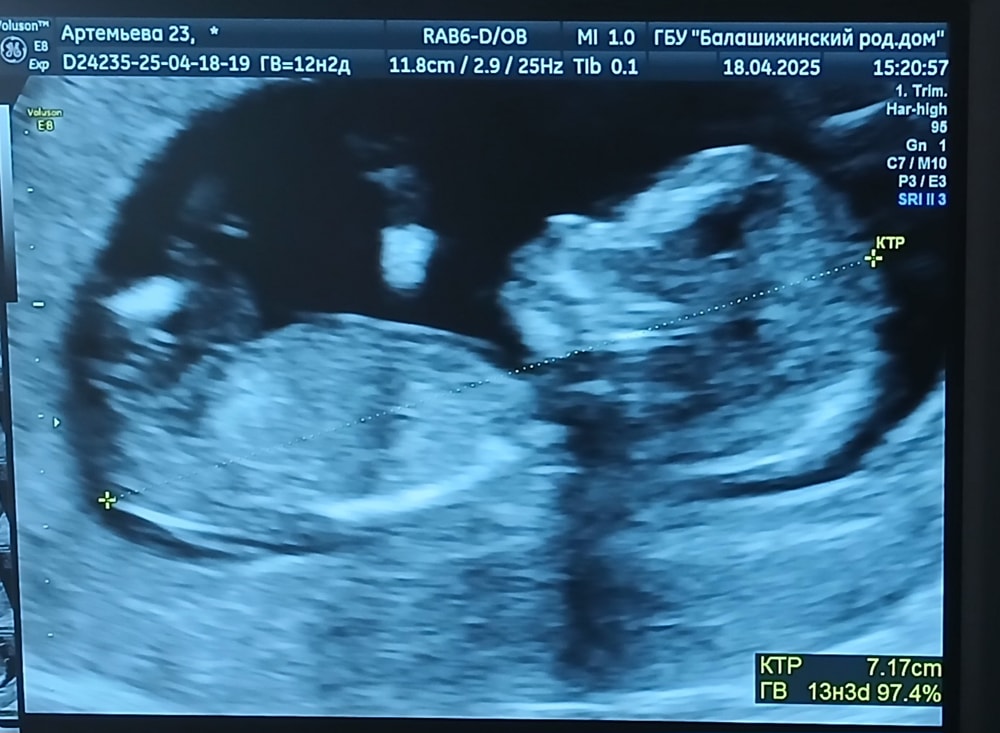

1 скрининг. 12 недель 🤰

Сегодня ровно 12 недель. По УЗИ все хорошо 🙏🏼 Жду результат анализа крови.

КТР 60

ТВП 1.6

Носовая кость визуализируется

ЧСС 153